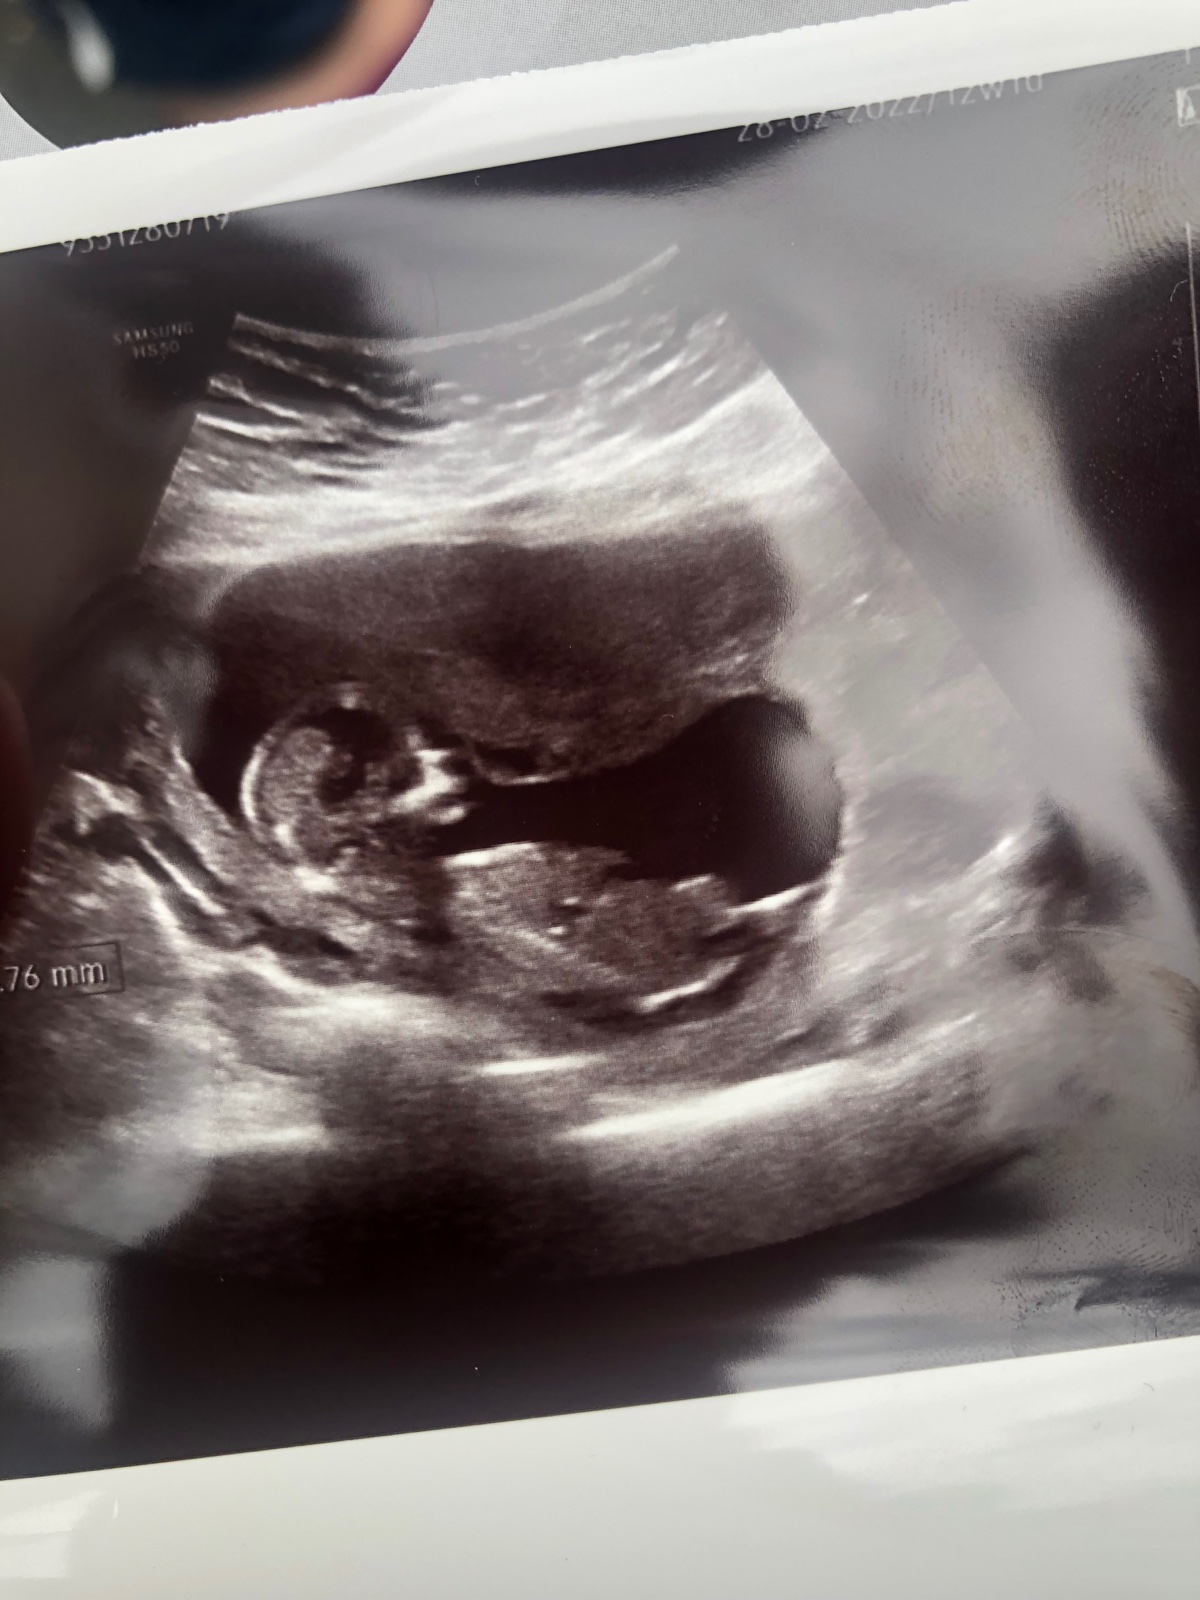

Dnes jsem byla na 1.screeningu, měla jsem s sebou i naší 5.letou cácorku a úplně jsem se pana doktora zapomela zeptat jestli by nepoznal pohlaví🙈 😂 hlavně že bylo vše v pořádku. Tak jen zkouším, jestli některá třeba nepozná podle fotky? Jestli třeba nemáte podobou fotečku a už víte ☺️ Je mi jasné ze to neni 100%, ale tak když už musím vydržet měsíc….😂 když jsem trubka..

@katuskabambulka to je škoda, on se doktor po zeptání dívá přímo mezi nožky, tohle je foto profilu a nepoznáš z toho nic

@katuskabambulka no takova ta kratka bila carka nahore jakoby mezi nozkama. To je ten pohlavni hrbolek /kustka ... A kdyz je vodorovna s pateri, tak holcicka a kdyz je smerem asi 30 stupnu nahoru, tak kluk. Rekli mi to dle ni na screeningu ve 13 tt jasne a od te doby to plati. Takhle se to v danych tydnech urcuje,zadny vnejsi pohlavni organ zatim neexistuje...

@katuskabambulka Tady na té fotce není vidět pohlavní hrbolek :( nemáš jinou fotku?